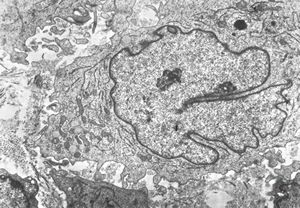

M, 11y. | mycosis fungoides v.s. - cerebriform nucleus of Sézary cell

F, 57y. | mycosis fungoides … cerebriform nucleus of Sézary cell

F, 37y. | mycosis fungoides … cerebriform nucleus of Sézary cell

M, 70y. | mycosis fungoides - Sézary cell

M, 70y. | mycosis fungoides - Sézary cell